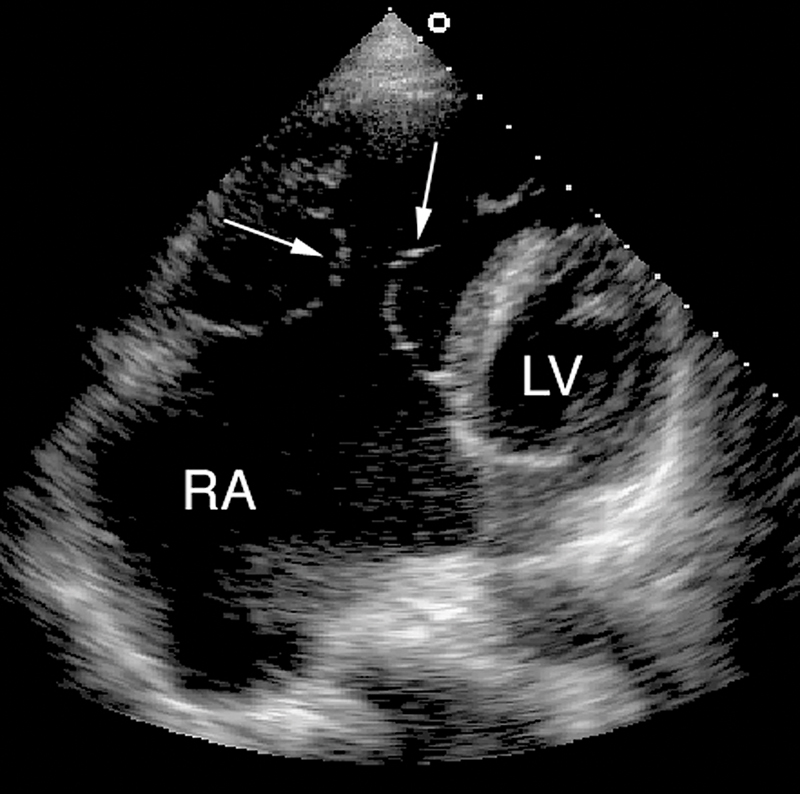

فحوصات تشخيصية لبعض امراض القلب والشرايين التاجية